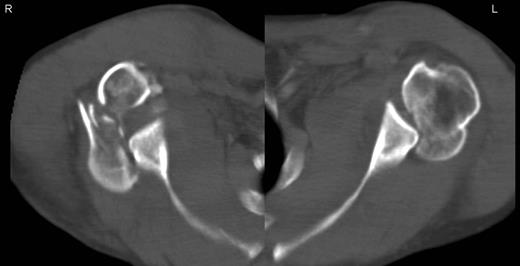

A 48-year-old patient was referred to a level I trauma center after the first incidence of an epileptic convulsion. The patient was alert and oriented with retrograde amnesia from the time of convulsion. Peripheral neurology was normal. The X-rays showed bilateral posterior shoulder dislocation with fractures of both humeral heads (Fig. 1). A CT of the head and both shoulders was performed to exclude intracerebral pathology and to achieve better demonstration of the shoulder fractures (Fig. 2). According to the AO fracture classification, he had a 11-C3.1 fracture on the left side and a 11-C3.3 fracture on the right side. The right side fracture was treated with a cementless hemiarthroplasty (OrTra®, Zimmer, Germany), while an open reduction and internal fixation (ORIF) with an angular stable plate (Philos®, Synthes, Germany) was performed on the left. Despite the high incidence for humeral head necrosis after ORIF in this fracture type, this option was chosen based on the young age of the patient. Postoperative X-rays and CT showed adequate positions of the implants (Fig. 3). The shoulders were immobilized in Gilchrist bandages followed by passive mobilization for the first 6 weeks by physiotherapy with a limitation for abduction and anteversion to 90°. There were no complications intraoperatively or in the first postoperative time. Patient was discharged after 8 days. Antiepileptic therapy was initiated with 5 mg clobazam and subsequent increasing doses over the following weeks. There were no more signs of epilepsy in the follow-up. A CT 4 months after operation showed dislocation of a fragment on the left side which was subsequently resected. At the 1-year postoperative review, the patient showed impingement of the left shoulder with abduction limited to 50° by both the plate and an osteophyte. Radiological assessment revealed signs of necrosis of the head. The plate was removed and the osteophyte resected. Eighteen months after injury, the left shoulder showed progressive avascular osetonecrosis of the head (Fig. 4) and after plate removal an inversed prosthetic replacement had to be performed (Fig. 5). At the last follow-up 3 years after injury, the patient was free of pain with a bilateral range of motion of 90° abduction and elevation.

Postoperative X-rays after hemiprothetic replacement on the right and angle stable plate osteosynthesis on the left side.